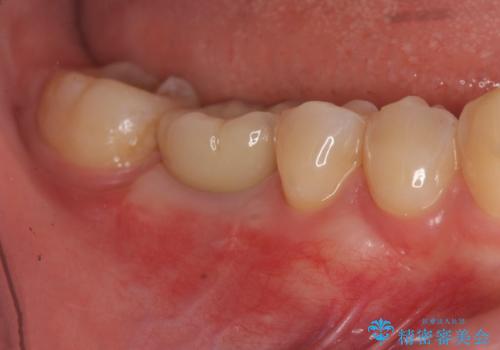

[ インプラントによる機能回復 ] 強い咬合力 放置した虫歯の治療

![[ インプラントによる機能回復 ] 強い咬合力 放置した虫歯の治療の症例 治療後](https://seimitsushinbi.jp/wp/wp-content/uploads/2022/07/5634e865a3957c7dade18cdc7bf6b192-500x350.jpg?v=1658988421)